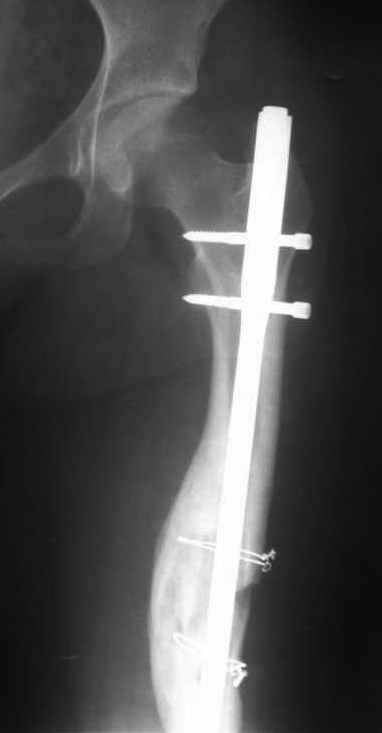

Здравствуйте коллеги. Сегодня поступил юноша 13 лет с повторным переломом правого бедра на стержне. Первый перелом был зимой 2003 году, синтезирован 2-мя стержнями Богданова. В июне 2003 года миграция стержней - стержни убраны. Повторный перелом в декабре 2003 года. Произведён МОС стержнем. Сегодня повторный перелом на стержне. Конечность уложена на шину Беллера. Господа, как можно удалить данный стержень? Чем предпочтительнее, на Ваш взгляд, синтезировать данный перелом у молодого растущего юноши с ожирением П ст.: пластиной, простым стержнем или стержнем с блокированием? ЭОПа у нас нет, поэтому пользуемся наборами ДЕОСТа с дистальной навигацией.

Снимок только при поступлении один.

Image(037)кор.jpg